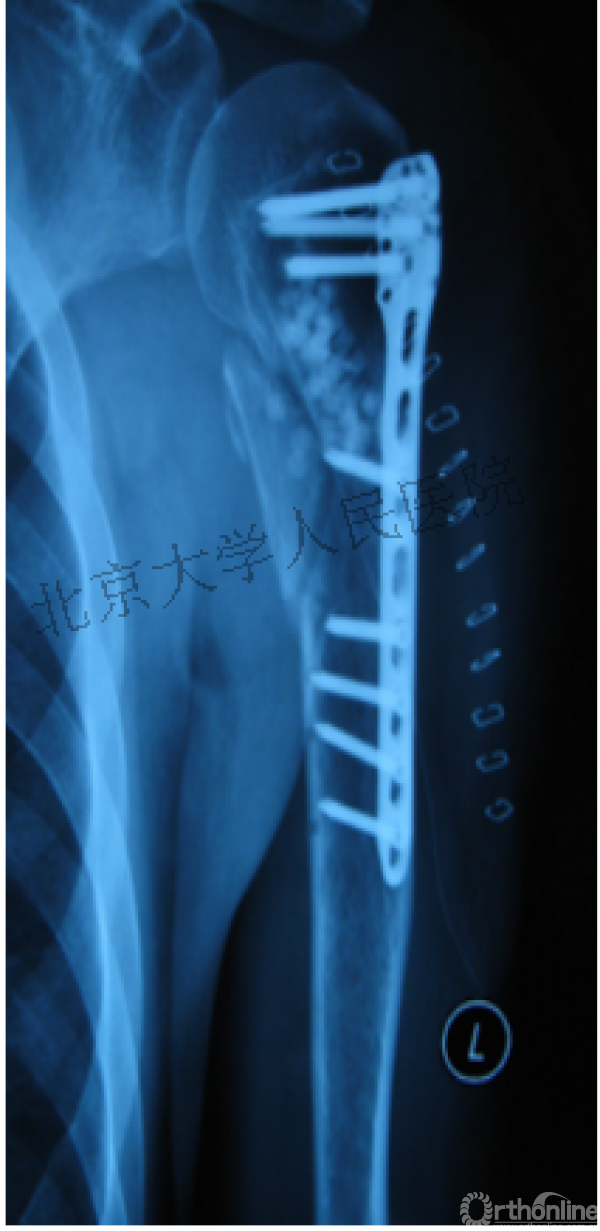

内侧皮质粉碎,低位外科颈骨折,肱骨头-干角维持困难。

术后复位丢失,肱骨头内翻畸形。

能否该偏心固定(钢板)为髓内固定,增加力臂?

早知今日,何必当初?

此时对比髓内钉是不是有很大优势?